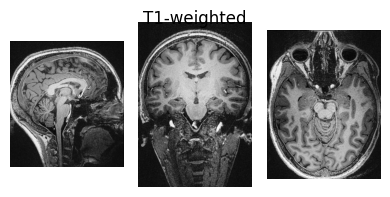

show_nii(glob("bids/sub-*/ses-*/anat/*T1w*nii*")[0], title="T1-weighted")